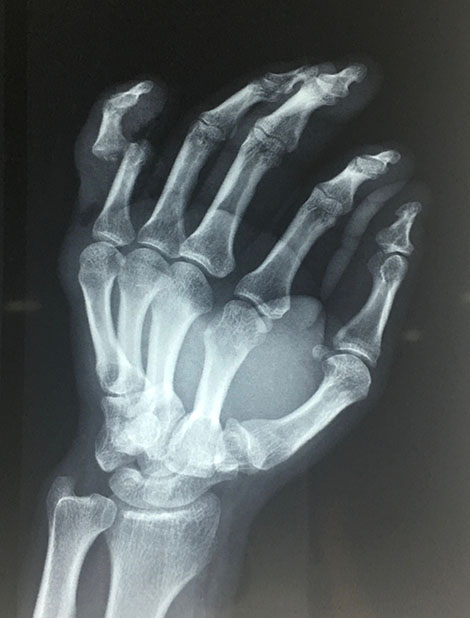

Nuestro paciente mientras ayudaba con el levantamiento de una maquinaria pesada sufre un accidente en que dicha maquina cae sobre su dedo meñique, tras esto se da cuenta que el dedo se ha estallado dejando ver su hueso y una importante herida, nota además deformidad del dedo, es llevado de inmediato a un hospital de la ciudad donde tras ser evaluado y hacerle radiografías le sugieren realizar amputación del dedo pero el paciente no la acepta y decide comunicarse conmigo como cirujano especialista en mano.

Evalué al paciente y siempre pensando en salvar el dedo de la amputación lo lleve a quirófano ese mismo día en horas de la noche, tras una buena limpieza de las heridas encontramos una luxación del dedo y redujimos la misma reparando la parte ligamentaria, mantuvimos al paciente hospitalizado durante 24 horas en que recibió antibióticos y controlamos el proceso de hinchazón del dedo.